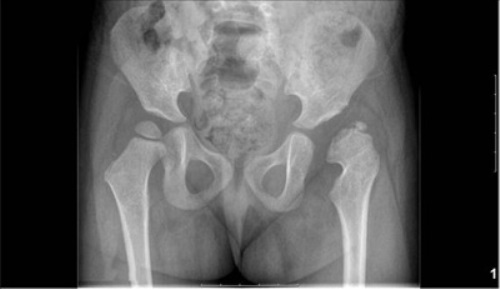

Интерпретация результатов рентгенобследования

При дисплазии (предвывихе) у ребенка патогномоничным признаком, который выявляется лишь рентгенспособом, выступает недоразвитие крыши вертлужной впадины на день рождения ребенка и запаздывание окостенения в будущем. Линия Шентона не нарушается.

Подвывихам рентгенологически свойственна опоздание оссификации ядра головки, сдвинутой кверху. Крыша вертлюжной впадины скашивается почти до 30 градусов, чем при нестабильности. При этом состоянии смещена линия Шентона.

Врожденный вывих рентгенологически выявляется по схеме Хильгенрейнера, позволяющей обнаружить недоразвитие сочленения и взаиморасположение бедренной головки и вертлюжной впадины.